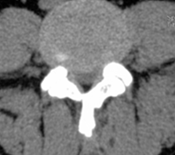

没有一种检查可以诊断腰椎间盘突出症。医生对患者进行详细的病史采集和临床体格检查后,要结合相关检查结果,综合进行诊断。CT检查显示椎间盘突出的部位、大小、形态和神经根、硬脊膜囊受压移位的形象,同时可显示椎板及黄韧带肥厚、小关节增生肥大、椎管及侧隐窝狭窄等情况,并可以三维技术重建椎管与根管的立体形态。此外,用水溶性造影剂做脊髓造影与CT检查结合,能提高诊断的准确性。MRI检查对椎间盘突出症的诊断具有重要意义。通过不同层面的矢状面影像及所累及椎间盘的多方位影像,可以观察病变椎间盘突出的形态及其与周围组织的关系。对于不能行MRI检查患者,也可以进行脊髓造影检查,准确性也很高。

腰椎X片、CT、MRI检查各有优缺点,具有互补性。患者患了腰椎间盘突出到医院就诊首先会行 X线片检查,可排除其它骨性病变。对于腰椎间盘突出症患者怀疑有骨质异常(狭部裂,骨骺离断)时考虑行CT检查。核磁共振成像技术(即MRI)是对于软组织(椎间盘突出部位,方向,脊髓神经根受压情况)检查方法,除了临床病史和体格检查,MRI已经是诊断腰椎间盘突出症的常用检查方法。